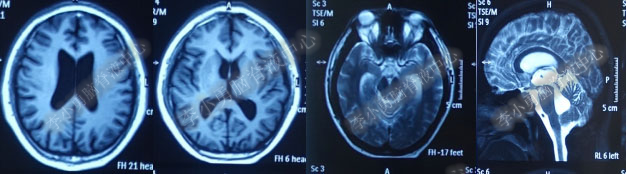

2017年6月19日(第1次内镜术后404天即一年零39天),因原症状加重,第2次住入该院。2017年6月20日(住院第2天),复查头部MRI(图-5)。

图-5:2017年6月20日头部MRI